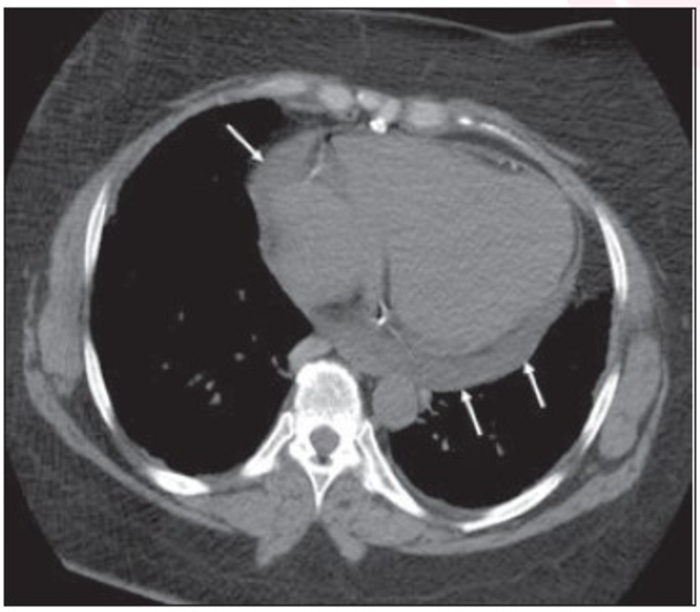

In a matched case-control study of 165 patients (70 female, 95 male; mean age, 67 years; 42 cases, 123 matched controls) who underwent major abdominal or pelvic surgery, independent predictors (p<.05) of postoperative mechanical ventilation using preoperative thoracic CT included bronchial wall thickening (exhibited odds ratio [OR]=4.8), pericardial effusion (OR=5.3), shorter lung height (OR=0.8 per cm increase), and greater anteroposterior chest diameter (OR=1.2 per cm increase).

“Bronchial wall thickening was the only qualitative parameter involving the lung parenchyma that differed between the case and control groups for both readers, with significantly increased need for postoperative mechanical ventilation in patients with bronchial wall thickening,” the authors of this AJR article added .